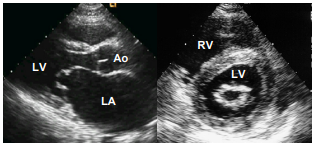

흉골연(parasternal), 심첨부(apical), 늑골하부(subcostal), 흉골상부(suprasternal)이다. 흉골연에서는 좌심실, 좌심방, 대동맥의 내경과 좌심실벽 두께, 좌심실 박출계수 등을 측정한다.

| 좌심실 구혈률 (Left Ventricular Ejection Fraction, LVEF %) |

좌심실의 수축기능을 측정하는 중요한 지표 LVEF(%) = 이완기말혈류량-이완기말혈류량/수축기말혈류량 → Normal : EF > 55% → Preserved : EF 50-55% → Reduced : EF < 45% |

| 좌심실 이완기말압 평가: E/E’ 정도 | E(초기 승모판 혈류속도) / E’(초기 승모판륜 속도)와의 비율 Normal : 5-10mmHg |